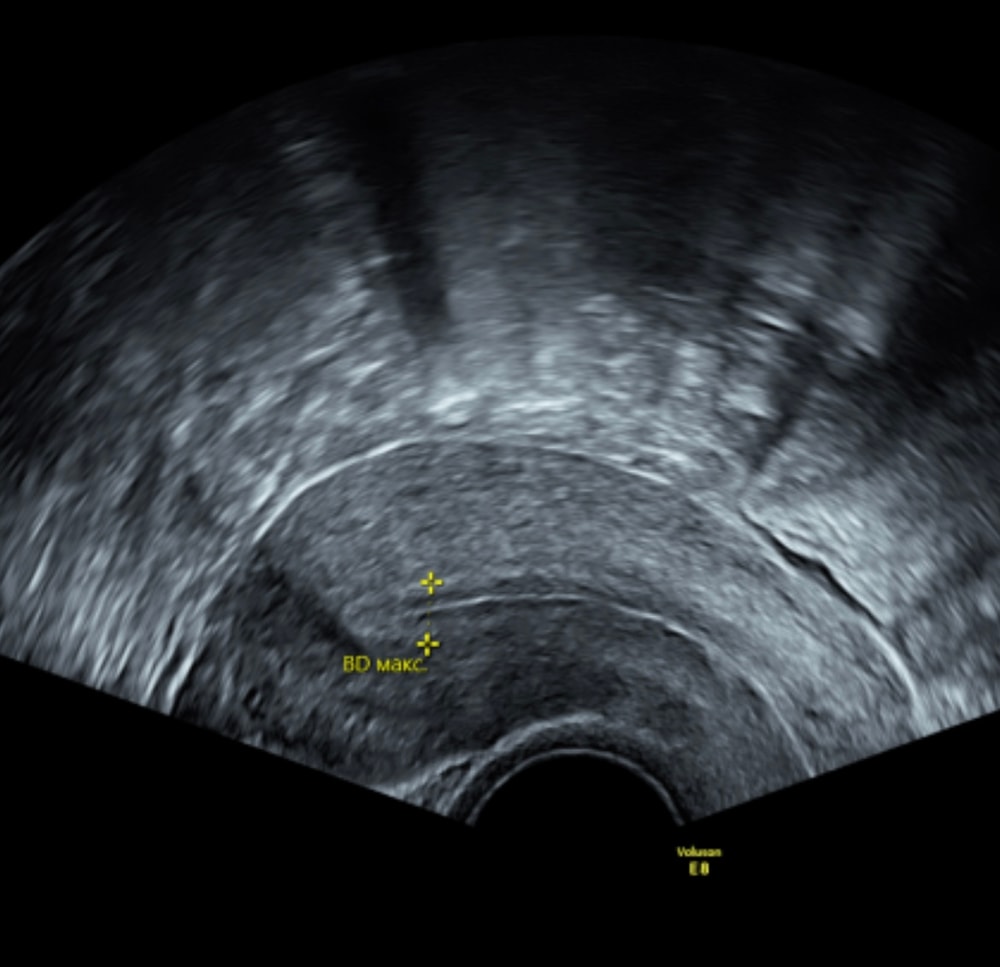

Трёхслойный он перед овуляцией, а после становится как раз гомогенным и пышным как подушка, для лучшей имплантации эмбриона.